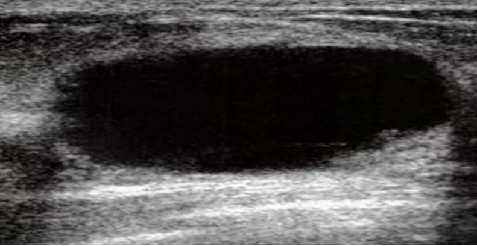

单纯囊肿 良性征象,恶性可能基本上为0,包括哪些可能病变呢?包括如:单纯囊肿,乳腺内正常淋巴结,乳腺假体植入,手术后稳定性的疤痕,脂肪小叶。 注意 #注意与腺纤维瘤鉴别: 这样的脂肪小叶,其实是正常的组织,但很容易误为病变,所以要找专业医生确认,不要太着急。需要强调的是,乳腺增生绝大多数不会癌变。 #有的结节分级与年龄有关: